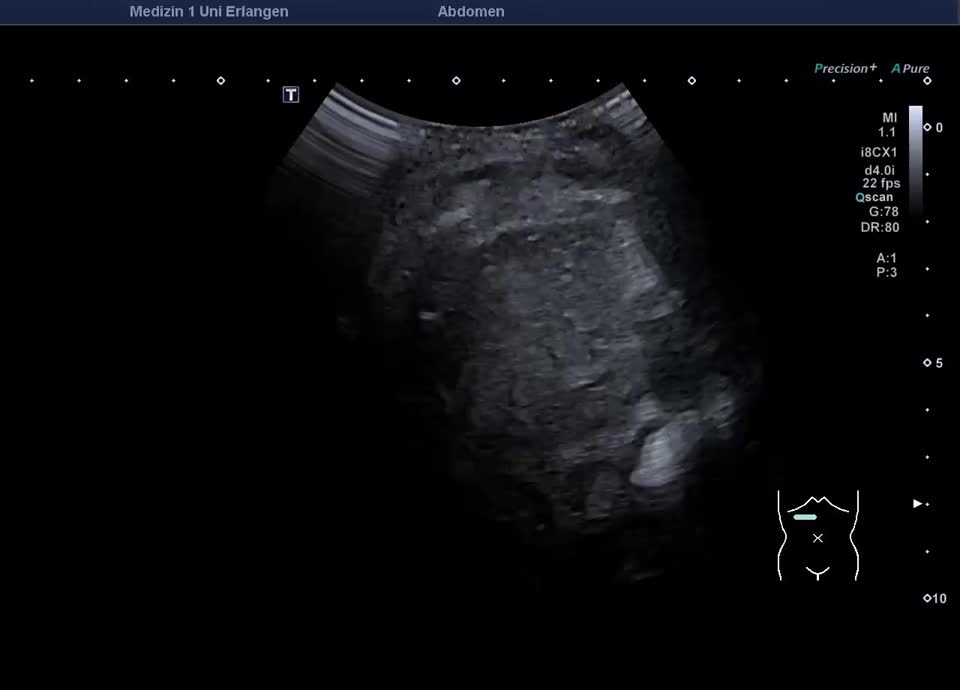

Ultraschall in der Notaufnahme: Gallenblasenempyem mit gedeckter Perforation (hochfrequenter Linearschallkopf)